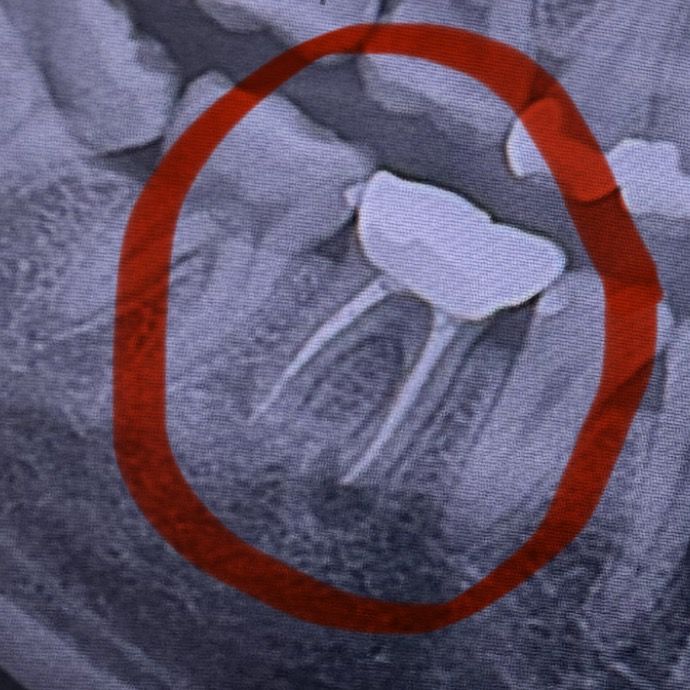

2년전에 크라운한 치아 임플란트 ㅜㅠ

2년전에 크라운했던 치아가 어제부터 너무아파서 치과를 가보니까 약복용후 낫지않으면 발치후 임플란트를 해야한다는데 방법이 없겠죠ㅜㅜ 약을 먹었는대도 지금 너무아파서 내일 병원 가보려고합니다!

현재 치아 뿌리 끝에 크게 염증이 생긴 것으로 보이며 재신경치료 혹은 발치 및 임플란트 해야할 것 같습니다.

신경치료하고 크라운 씌운 치아입니다. x-ray 상에서 치아뿌리 끝에 염증이 생겨 있습니다. 일단 약 복용하고 염증 가라앉혀 보아야 합니다. 염증이 가라앉으면 발치 안하고 버텨 볼 수도 있습니다.

치아 뿌리끝에 염증이 생긴거 같습니다. 염증이 활성화 된상태가 아니라면 크게 문제는 없지만 통증이 잇다면 염증이 활성화된 상태라서 재신경치료를 해보거나 발치를 하셔야될것같습니다.

이미 신경치료가 되어 있는 치아이나 현재 사진상으로는 치아 뿌리끝으로 염증이 남아있는 상태로 재신경치료 내지는 치근단절제술이 필요할 것 같습니다.

사진으로 봤을경우에는 이전에 신경치료를 한 치아의 뿌리에 염증이 생긴것으로 보입니다. 약복용보다는 재신경치료를 통해서 신경관의 감염을 제거해보는것이 좋습니다.

자세한 확인을 위해서 치과에서 진료를 받아 보는것을 권유드립니다.